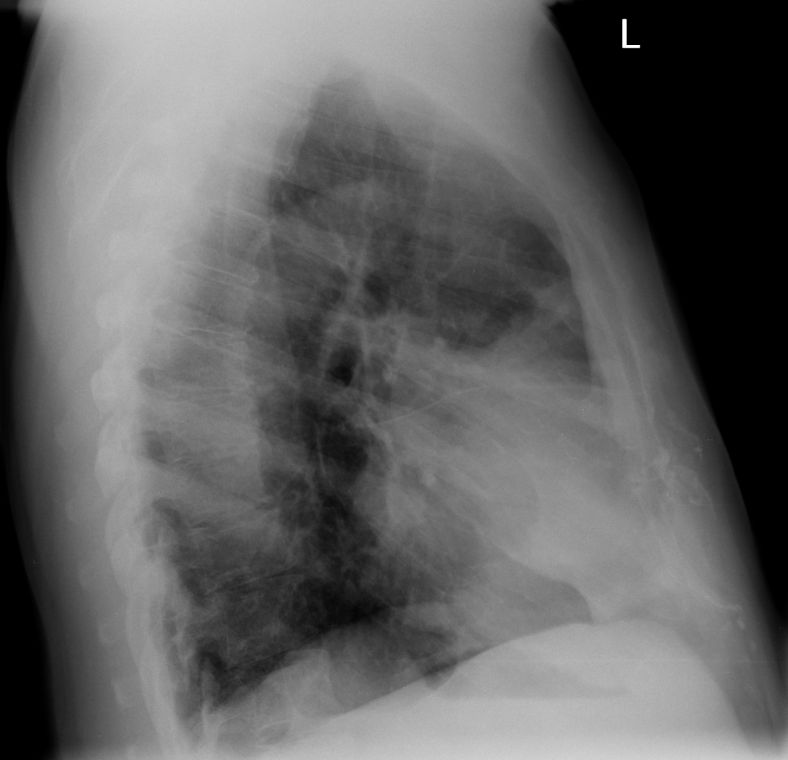

| B1-Thymom | 69-jähriger Mann, bei dem vor einer geplanten orthopädischen Operation eine Lungenaufnahme gemacht wurde. Es fand sich eine Raumforderung im vorderen Mediastinum rechts und ein kleinerer Befund rechts dorsal. Histologische malignes Thymom Stadium IV nach Masaoka. Nach 4 Zyklen Cisplatin, Doxorubicin, Cyclophosphamid partielle Remission. Nach Radikaloperation mit Pneumektomie postoperative Bestrahlung. | |||